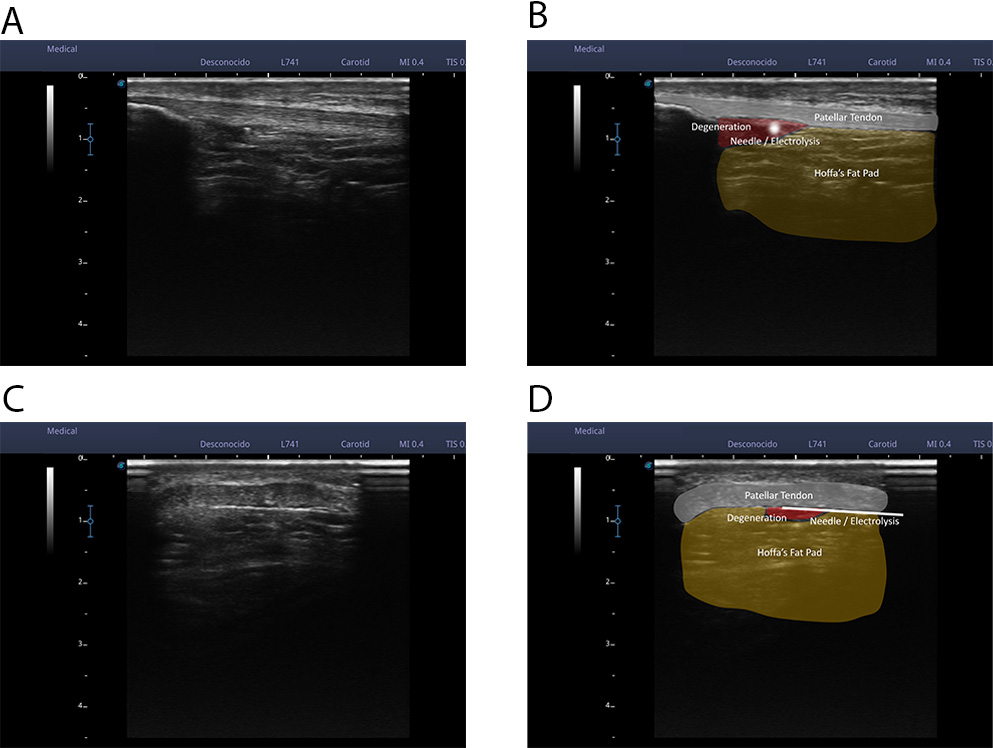

In all cases the tendon approaches were superficial, on it superficial interface

and on it deep interface due to the relationship with the Hoffa fat. The needle

insertion area was sterilized with chlorhexidine. Sterile ultrasound gel was then

applied to obtain the reference ultrasound image. Ultrasound examination was then

performed until a clear cross-sectional image of the destructured area or the

area of local pain of the patellar tendon was obtained. Once the image was

obtained, using the scale to the left of the ultrasound image, the distance of

the superficial and deep interface of the patellar tendon from the probe was

calculated. With these reference values, the needle was introduced completely

parallel to the probe (in in-plane approach), from the lateral margin of the

tendon at the necessary distance to access the superficial or deep interface of

the tendon (Figs. 1,2). We use the electromedical device EPTE System, to supply

in each approach a galvanic current with 350

Fig. 2.An ultrasound examination was performed until a clear cross-sectional image of the unstructured area or the area of local pain of the patellar tendon was obtained. Once the image was obtained, using the scale to the left of the ultrasound image, the distance of the superficial interface and the deep interface of the patellar tendon from the probe was calculated. With these reference values, the needle was introduced completely parallel to the probe (an in-plane approach), from the lateral margin of the tendon at the necessary distance to access the superficial interface or the deep interface of the tendon (A,B). In these 2 images we can see a real image of an ultrasound cross-section of the patellar tendon (A) and a representation of the tissues that can be observed (B); patellar tendon, Hoffa fat, hypo-echoic area, and needle. (C,D) In these 2 images we can see a real image of a longitudinal ultrasound cut of the patellar tendon (C) and a representation of the observable tissues (D); patellar tendon, Hoffa fat, hypoechoic area, and needle.